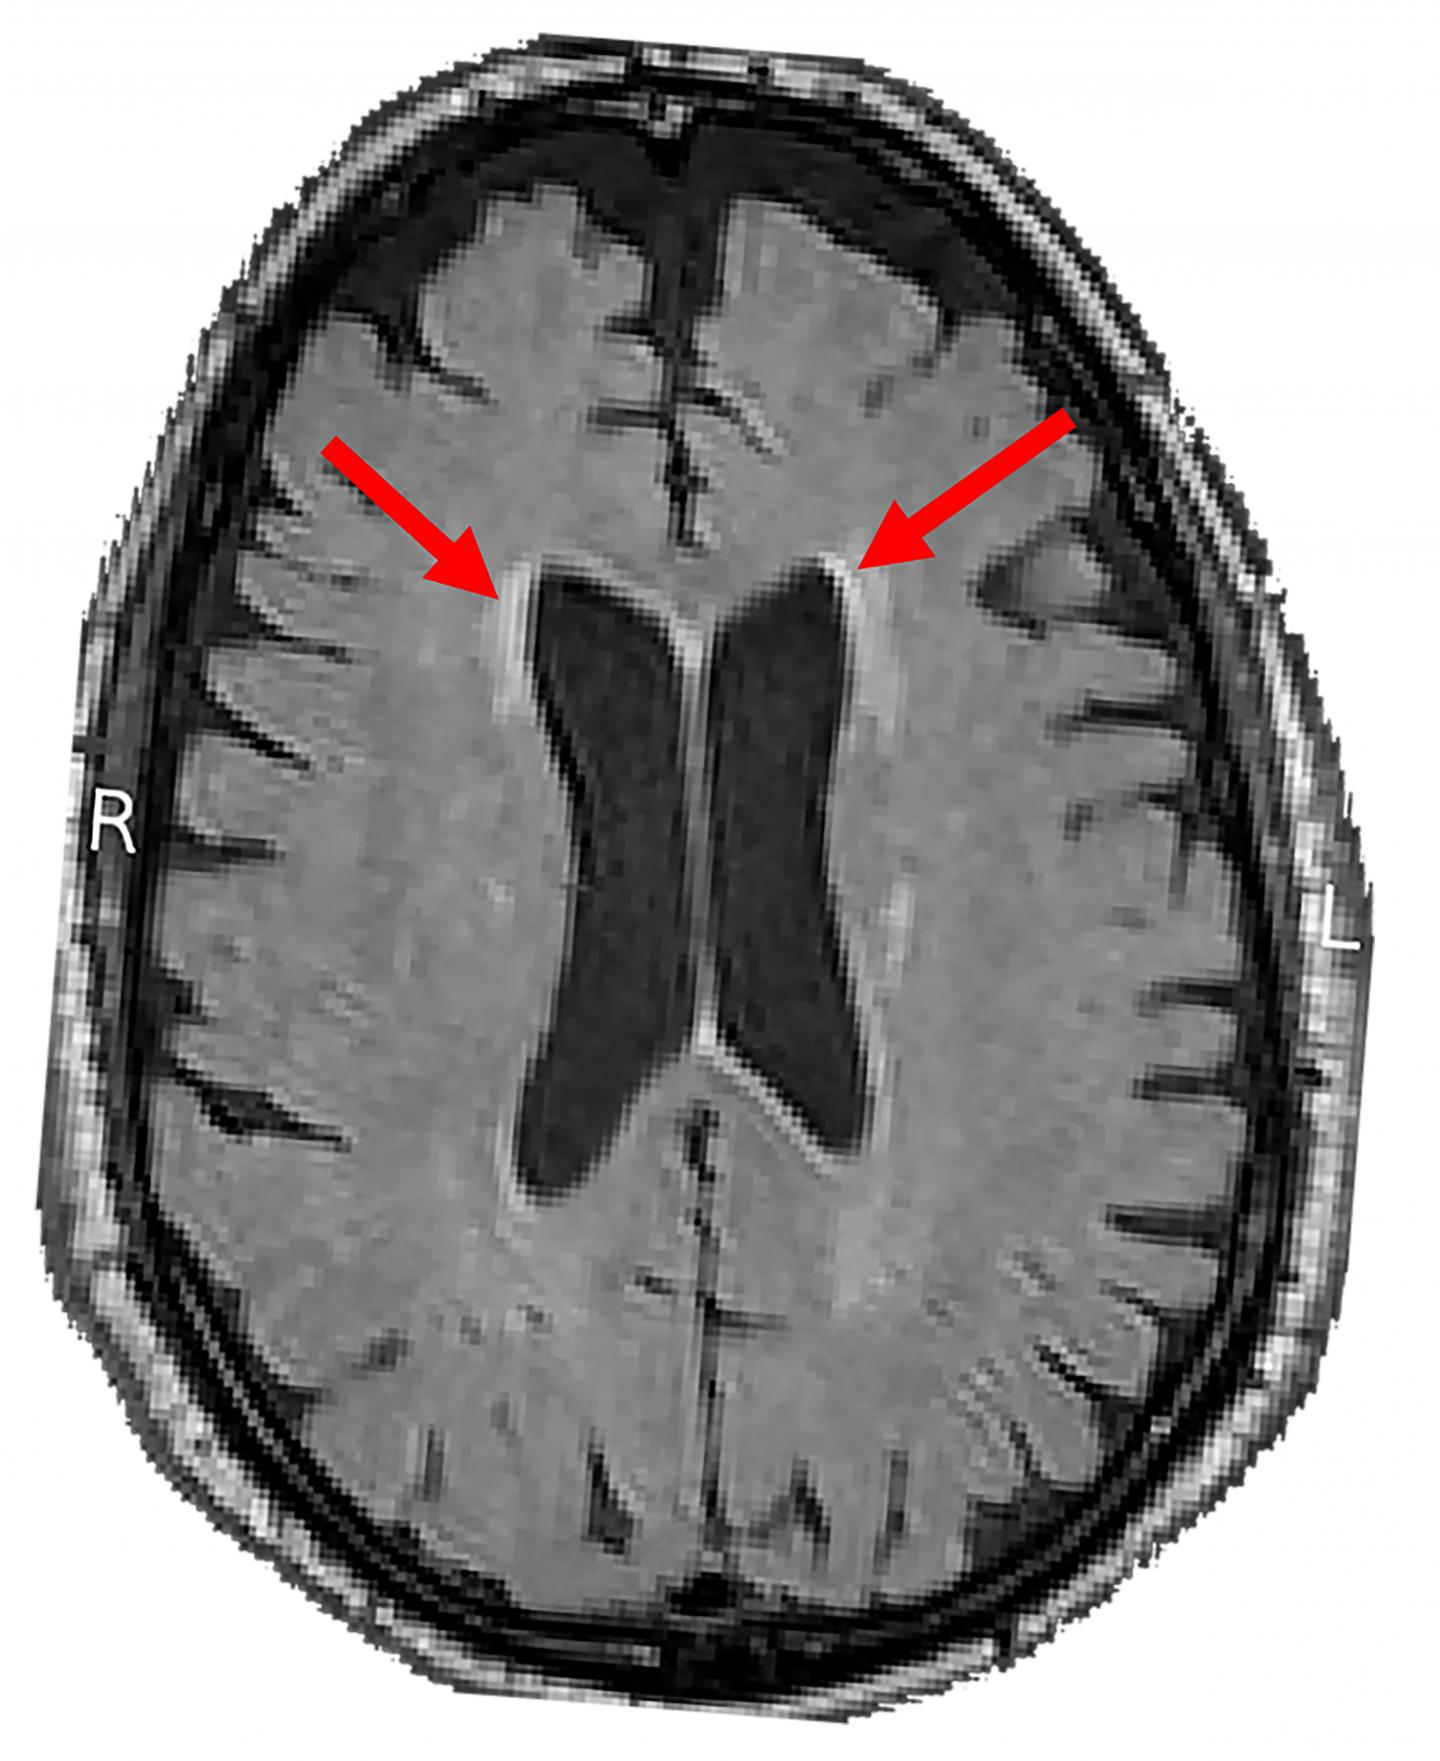

image: NIH funded study found link between blood pressure and white matter lesions. Arrows highlight examples of lesions seen on magnetic resonance imaging brain scans.

Brain white matter is made up of billions of thin nerve fibers, called axons, that connect the neurons with each other. The fibers are covered by myelin, a white fatty coating that protects axons from injury and speeds the flow of electrical signals. White matter lesions, which appear bright white on MRI scans, represent an increase in water content and reflect a variety of changes deep inside the brain, including the thinning of myelin, increased glial cell reactions to injury, leaky brain blood vessels, or multiple strokes. These changes are associated with high blood pressure, or "hypertension".

The NIA and NINDS supported sub-study, SPRINT MIND, enabled scientists from 27 clinical sites to examine the effects these treatments had on the brain by measuring cognitive function and acquiring MRI scans on a subset of SPRINT participants. The researchers compared brain scans of 449 participants that were taken at enrollment and four years later. During this time, the average increase in total volume of white matter lesions on scans of the intensive treatment group was 0.92 cm3, which was less than the 1.45 cm3 seen on scans from the standard treatment participants.